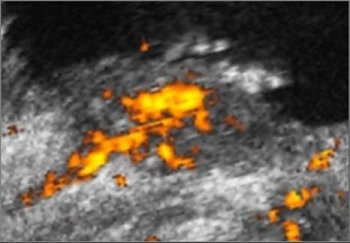

Freehand scanning was used for 3D data acquisition, and surface rendering and multiplanar reconstruction for 3D data analysis. Power Doppler ultrasound was used to differentiate the extent of infiltration. The criteria for staging were based on the vascularity of the tumor's basement. The gold standard was the histomorphology results.

| Power Doppler ultrasound criteria for staging vascularity of the tumor basement. Above, submucosal vessels; second, half muscle wall vascular. Below, whole muscle wall vascular; second image, few vessels in the perivesical walls; third image, massive flow in the perivesical fat. Images courtesy of Dr. Veronika Gazhonova, Russian President Medical Center and Russian State Medical University. |